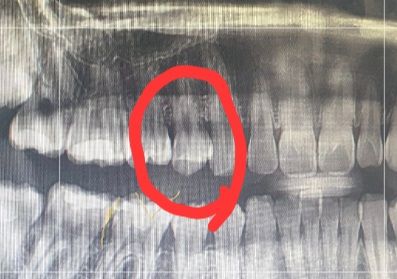

동그라미친 곳입니다 겉으로는 멀쩡해서 구분하기 어렵고 신경치료 해야하는 의견도 있고 신경치료말고 간단한 치료를 하라는 말도 있어서 의견 물어보기 위해 질문남깁니다.

• 1번 째 사진